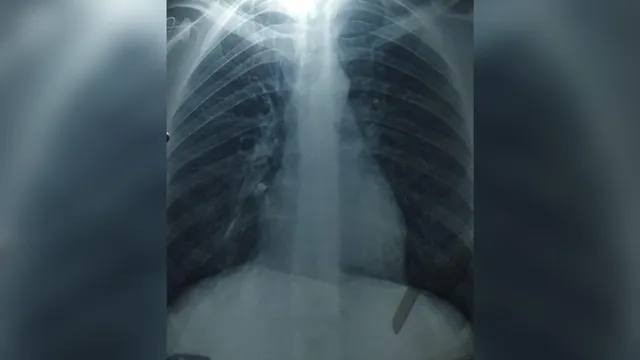

- Artur underwent a wisdom tooth extraction and one tooth was accidentally aspirated.

- He developed severe hiccups and chest pain, prompting him to seek medical evaluation.

- Doctors confirmed the aspiration and successfully removed the tooth from his lung.